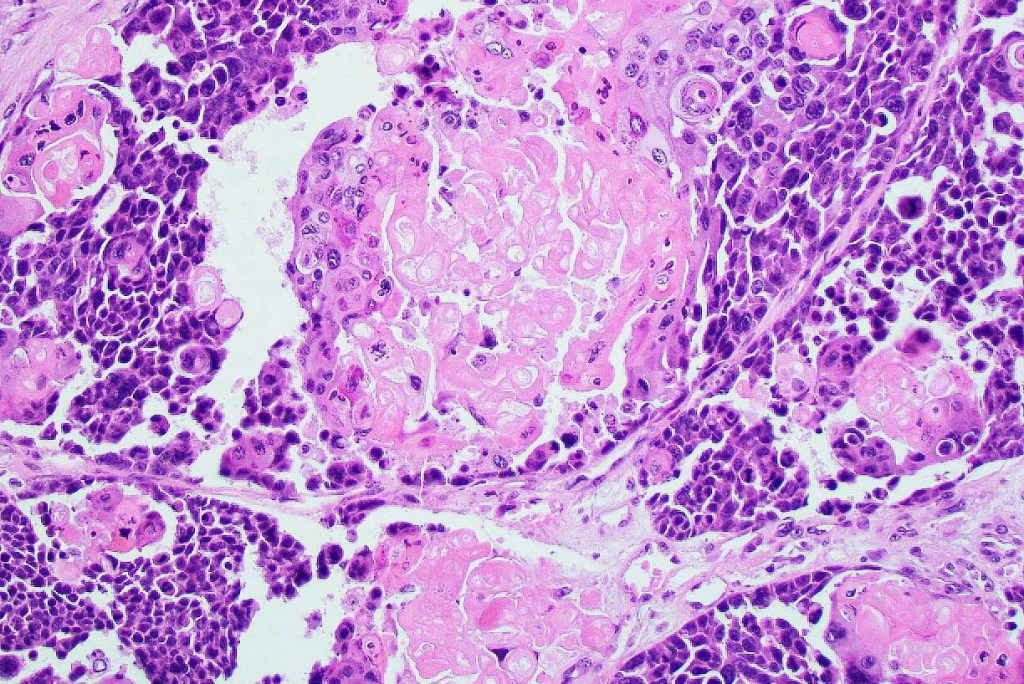

•Lobular or a diffusely infiltrating growth pattern. Composed of pleomorphic hyperchromatic, basaloid cells with nucleolar prominence, abundant mitoses & atypical mitoses (brisk mitotic activity should not be used as a defining feature of matrical carcinoma since in the evolving phase mitoses are typically very numerous in pilomatricoma)

•Necrosis common

•Matricial & supramatricial differentiation

•Squamous differentiation